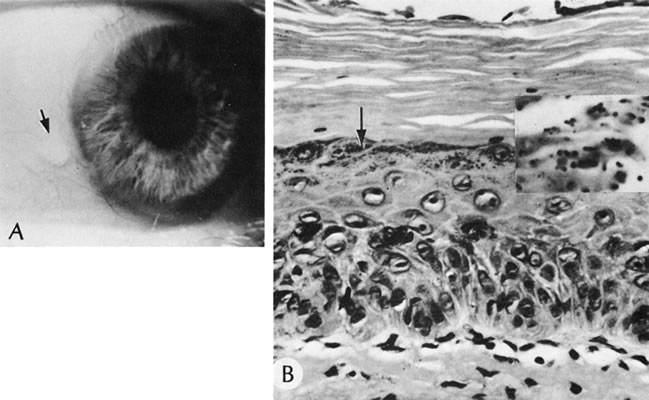

AXENFELD'S ANOMALY

Isolated Axenfeld's anomaly (posterior embryotoxon) consists of a clinically prominent Schwalbe's line (terminal end of Descemet's membrane) plus a variable number of iris processes extending from the peripheral iris to Schwalbe's line (Fig. 6). The condition is most likely a developmental arrest, late in gestation, of tissues derived from neural crest cells.66 The line appears as a deep linear opacity of the peripheral cornea of variable prominence and extent and is most often found temporally. The prevalence rate is approximately 15% to 25%.67,68 No race or sex predilection exists. Although the majority of the eyes are normal, an associated partial iris coloboma and other anomalies may occur.68 Axenfeld's anomaly may be associated with non-ocular abnormalities as part of Axenfeld-Rieger's syndrome (see later).

Fig. 6. Axenfeld's anomaly (posterior embryotoxin). A. The only abnormality visible from the 2-o'clock to 4-o'clock positions adjacent to the limbus is a “ropy” corneal opacity. The other eye is normal. B. A corneal opacity is present over 360 degrees near the limbus at the level of Descemet's membrane. C. Scanning electron micrograph shows the iris processes spanning the angle and attaching to the anteriorly displaced Schwalbe's ring. Artifactually broken ends of the iris processes are indicated by the arrows. D. Macroscopic appearance of the iris processes attaching to Schwalbe's ring. E. Iris processes attach to the anteriorly displaced Schwalbe's ring. (Courtesy of SEI Photoarchives.)

Histologically, Axenfeld's anomaly consists of dense collagen and ground substance covered by a monolayer of flattened endothelial or spindle-shaped cells at the terminal end of Descemet's membrane. The endothelium is contiguous with the endothelium covering the trabecular beams.68 Associated iris processes are composed of normal-appearing iris stroma.